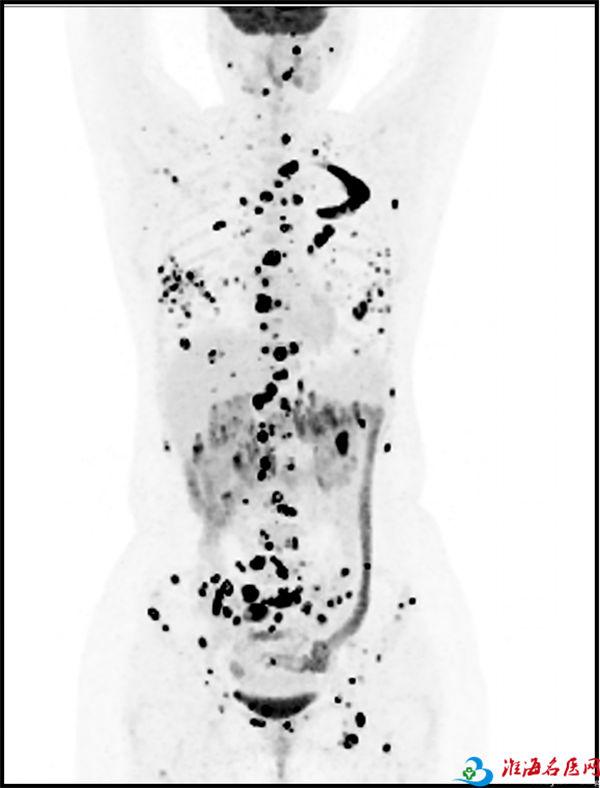

比如,下面这张18F-FDG PET图像,PET非常灵敏地将患者身体里的大小不同的病灶都检测出来(下图中那些散乱的黑点),给临床医生提供更全面、直观的印象,帮助医生选择更合适的治疗方案。